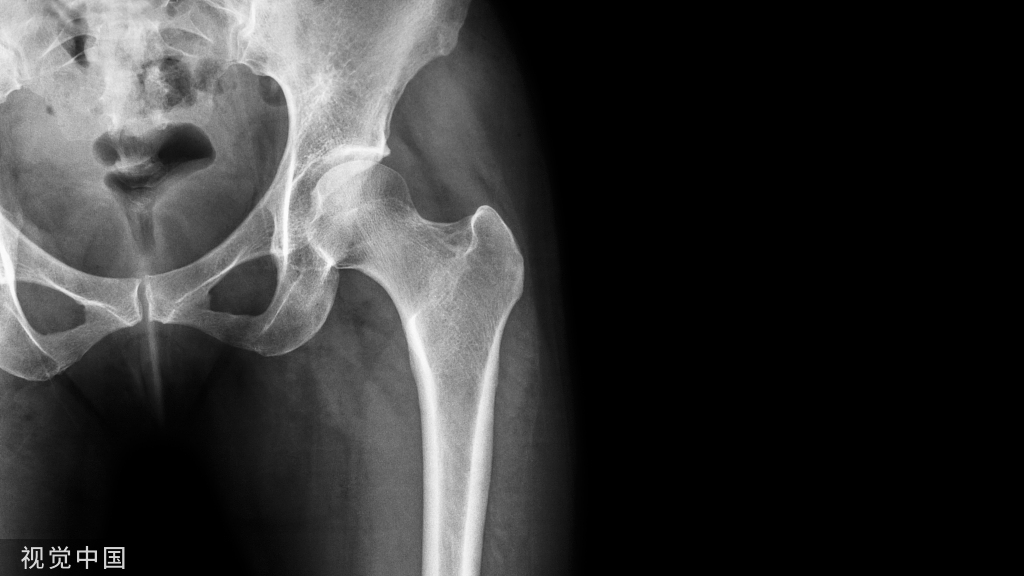

从长远来讲,新冠病毒感染导致骨质流失的问题不需要过度担心,因为治疗骨质疏松症除了抑制破骨细胞的活性药物外,中医中药也发挥着重要的作用。中医的整体观和辨证论治,对于降低新冠长期症状出现的频率以及减轻症状的严重性方面有积极的意义。张伯礼院士曾明确表示,因为普遍使用中医药,我国感染新冠后遗症比欧美等国少得多轻得多,得益于我国的中医药全程介入新冠的防治以及康复阶段,这是非常重要的一点。

中医理论认为“肾虚髓枯”是“骨痿”“骨枯”等疾病最重要的发病机制。根据中医药“肾主骨”“脾主肌肉”及“气血不通则痛”的理论,治疗骨质疏松症以补肾益精、健脾益气、活血祛瘀为基本治法。药物干预可选择《原发性骨质疏松症中医临床实践指南》中推荐的中成药骨疏康胶囊进行骨质疏松症的防治,有效的抗骨质疏松症药物可以增加骨密度,改善骨质量,显著降低骨折的发生风险。